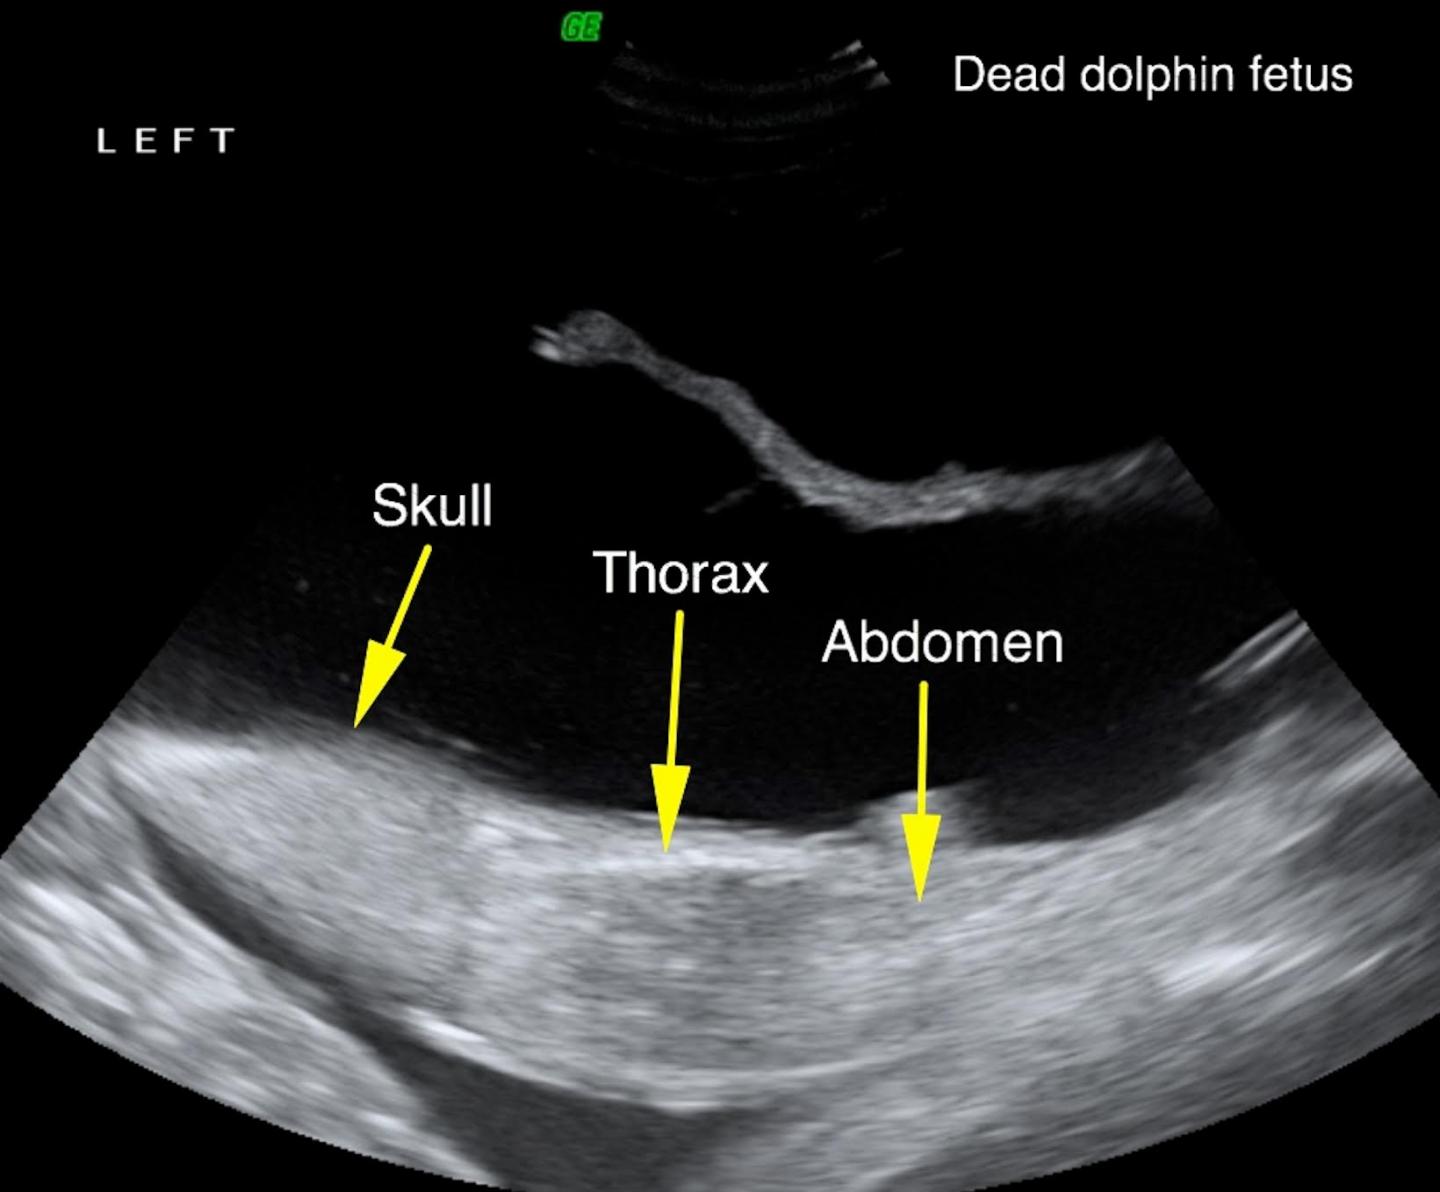

From www.eurekalert.org

Y31 Dead Fetus Ultrasound [IMAGE] EurekAlert! Science News Releases What Do They Do With Dead Fetus  If loss occurs before week 20 of pregnancy (gestation), it’s called a miscarriage. Stillbirths involve fetal death after week 20, while miscarriage involves the fetus passing away before week 20. Stillbirth is death of a fetus at 20 weeks of pregnancy or later (or after 28 weeks in some definitions). Stillbirth is a common term for death of a fetus. What Do They Do With Dead Fetus.